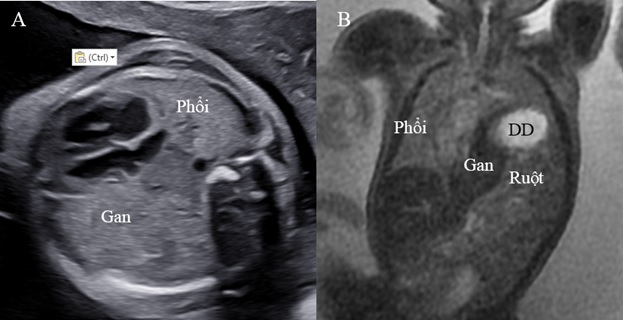

Hình 2. Thoát vị hoành trái. A: Mặt cắt ngang bụng không thấy dạ dày. B: Mặt cắt ngang 4 buồng tim có hình ảnh dạ dày (DD) và ruột đẩy sát tim qua sát thành ngực phải; phổi phải bị chèn ép.

Hình 3. Thoát vị hoành trái có kèm thiểu sản tâm thất trái

MRI là phương tiện chẩn đoán hình ảnh cao cấp giúp đánh giá thể tích phổi bên thoát vị và cả bên đối diện chính xác hơn siêu âm. Chụp cộng hưởng từ cũng cho phép đánh giá tốt về thoát vị gan, tỷ lệ gan trong lồng ngực vì độ tương phản của phổi và gan có sự khác biệt rõ trên MRI chứ không tương tự như trên siêu âm thang xám. Nên hiện nay ở một số trung tâm tiền sản, MRI được chỉ định thường quy cho CDH để giúp chẩn đoán và đánh giá tiên lượng chính xác hơn.

Với CDH bên trái, gan có thoát vị lên lồng ngực là một yếu tố dự báo độc lập bên cạnh kích thước phổi (như o/e LHR). Về mặt lý thuyết, có thể dùng siêu âm đánh giá phần gan trong lồng ngực, Nhưng trên siêu âm, độ hồi âm của gan rất giống với phổi nên sự đánh giá chính xác phần gan trong lồng ngực có phần hạn chế. MRI giúp đánh giá chính xác hơn vì tín hiệu của gan và phổi khác biệt rõ. Thể tích phổi toàn phần quan sát/mong đợi trên MRI (TLV) được dùng để đánh giá tiên lượng trong trường hợp thoát vị có gan lên.

Hình 6. A: Phản âm của gan và phổi tương tự nhau trên siêu âm 2D. B: Có sự khác biệt tín hiệu của phổi, gan, ruột và dạ dày trên MRI